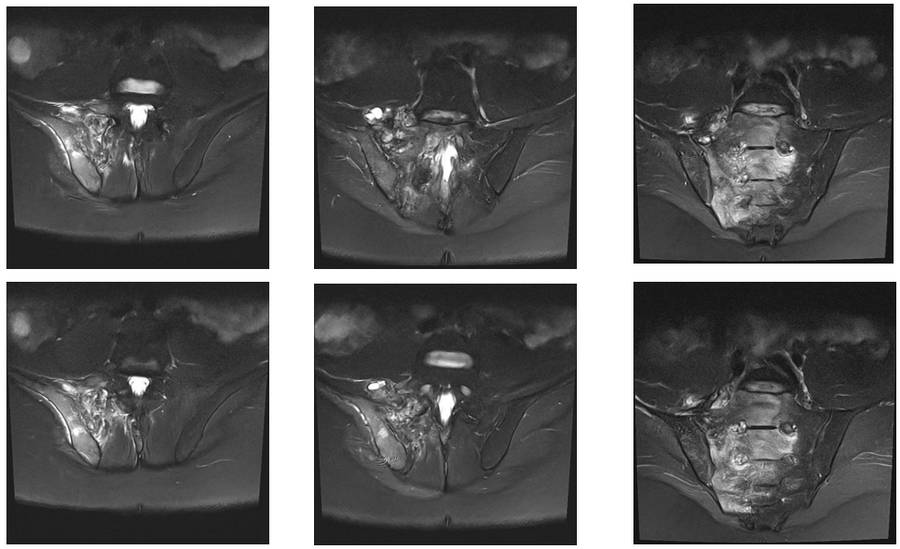

Ameliyat Öncesi: MR’da sağ iliak kanat posterior sakroiliak bölge üst kısım ve sakrumun tamamına yakınını kapsayan tümör dokusu ve çevreleyen ödem görülmekte